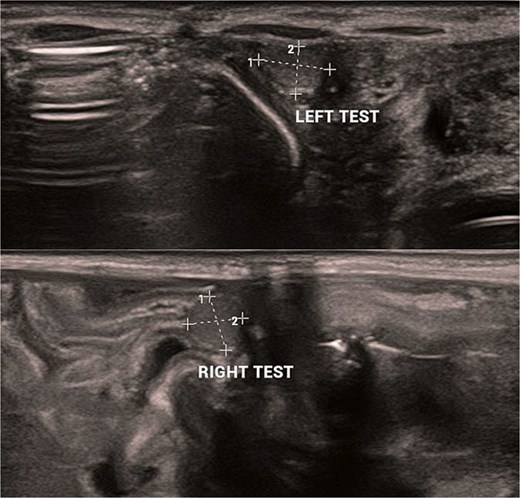

Abdominal and scrotal ultrasonography demonstrated multilocular cystic hydronephrosis with thinning of renal parenchyma, extending into the pelvis, and absence of testes within the scrotum. Both testes were located intra-abdominally between bowel loops (left 7 × 4.5 mm, right 6 × 5.5 mm) (Figs 2 and 3). Abdominal X-ray after percutaneous nephrostomy with contrast revealed pooling in both kidneys without ureteric passage, suggesting bilateral ureteropelvic junction obstruction (UPJO) (Fig. 4).